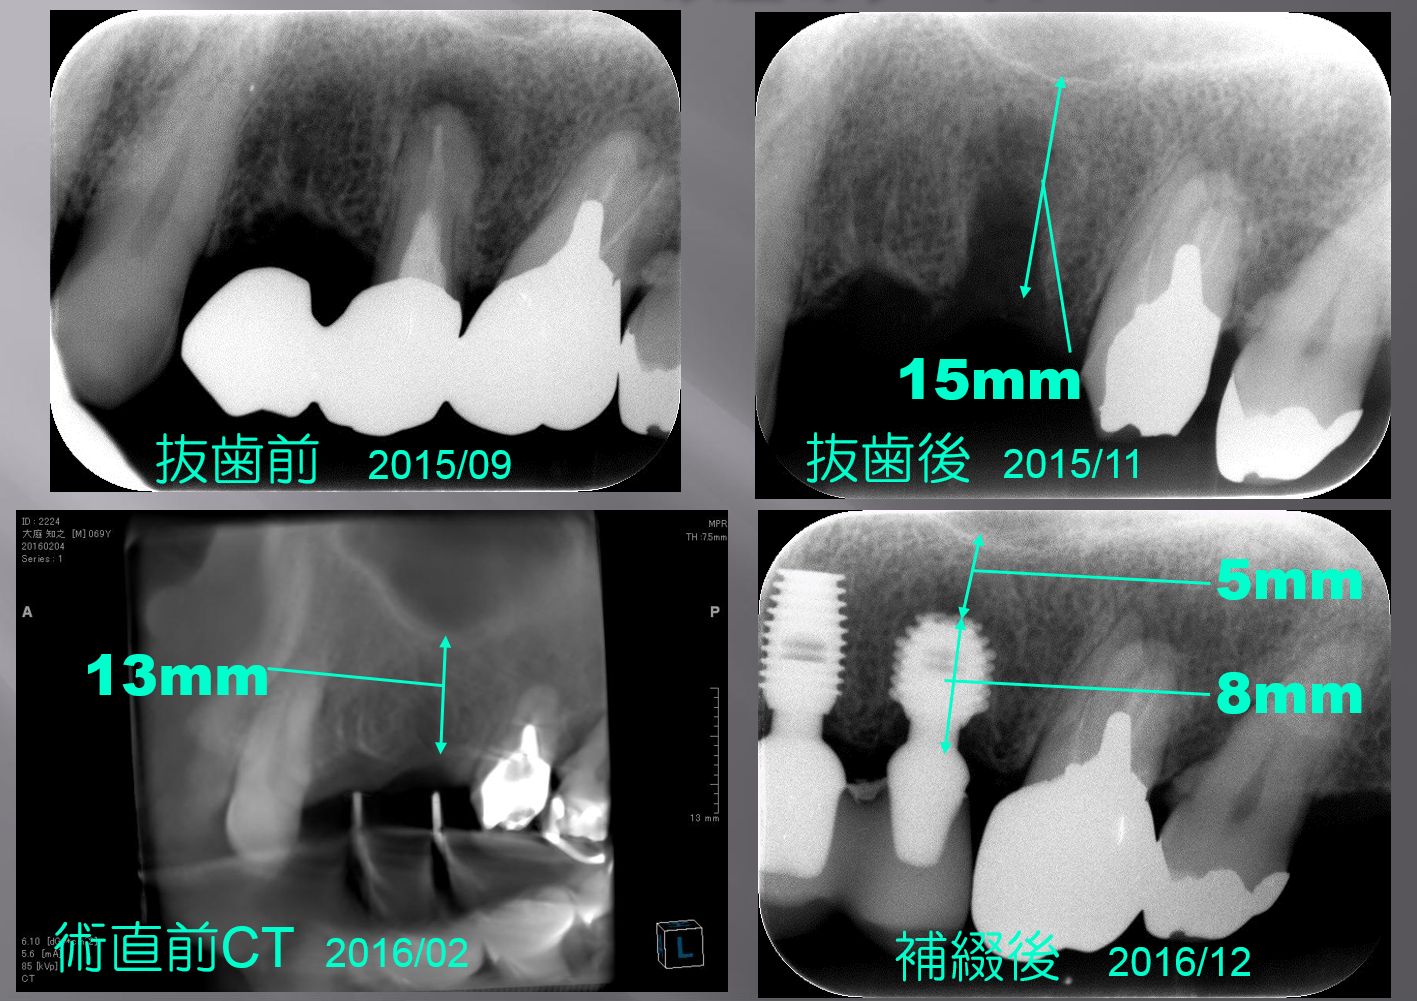

まず左上の写真から説明しましょう。上の歯に3本つながったブリッジが入っていますが、一番左側の歯が割れてしまいまして 痛みが止まらないために抜歯せざるを得なくなっていました。一般のブリッジは真ん中が抜歯されていて両端に支えの歯が残っていることが多いのですが、この場合は支えの歯が片方しかなく中央の歯に負担がかかってわれたものと思います。患者様が抜歯とインプラントを決断するまでに2ヶ月かかってしまいました。2ヶ月後に抜歯した直後のレントゲン写真が右上の写真です。

上顎洞の一番低いところから歯を支える歯槽骨の上までの距離が15mmくらいでした。

一般に抜歯をすると穴が残ります。穴があるままではインプラントが不安定になりすぐにはインプラントを入れません。穴の中に次第に骨ができて完全に骨になるまで半年近く待ちます。しかし、その際にはやや骨が小さくなって、高さも下がりますし幅も狭くなります。この場合には、抜歯から4ヵ月後で15mmが13mmにまで下がりました。

インプラントにも色々なサイズが準備されていて、一般に10mmから12mmが最も使用頻度が高いです。13mmあれば長いほうの12mmでも入ります。もしも、12mmを入れていれば残りの骨の厚みは1mmです。最低でも1mmの余裕がないとギリギリ過ぎるとドリルがオーバーした時に鼻に抜けてしまいます。このケースでは、6mmの長さのインプラントを2mm骨縁下の入れましたので残りが5mmと余裕があります。上顎洞底挙上術どこのメーカーでもこれだけあれば入りますが、脱落しにくいという理由から私は上顎にはバイコンと言うメーカーのショートインプラントを入れています。元々ショートインプラントは骨の高さが少ない時でも、骨を作る必要がありません。

最も短い物で5mmというサイズのインプラントがありますから、最低6mmまでは骨を造らずに入れることが可能です。一般のメーカーでは最も短いサイズはほぼ8mm~8.5mmとなっていますからこの場合は9mm以下ならば上顎洞底挙上術をする必要性が出てきます。実際、当医院で上顎洞底挙上術をする症例は全体の半分から3分の1ぐらいにもなります。上顎洞底挙上術をされない先生方では、インプラントができないと言われる事もしばしば有りますが、当医院では可能ですのでご相談ください。